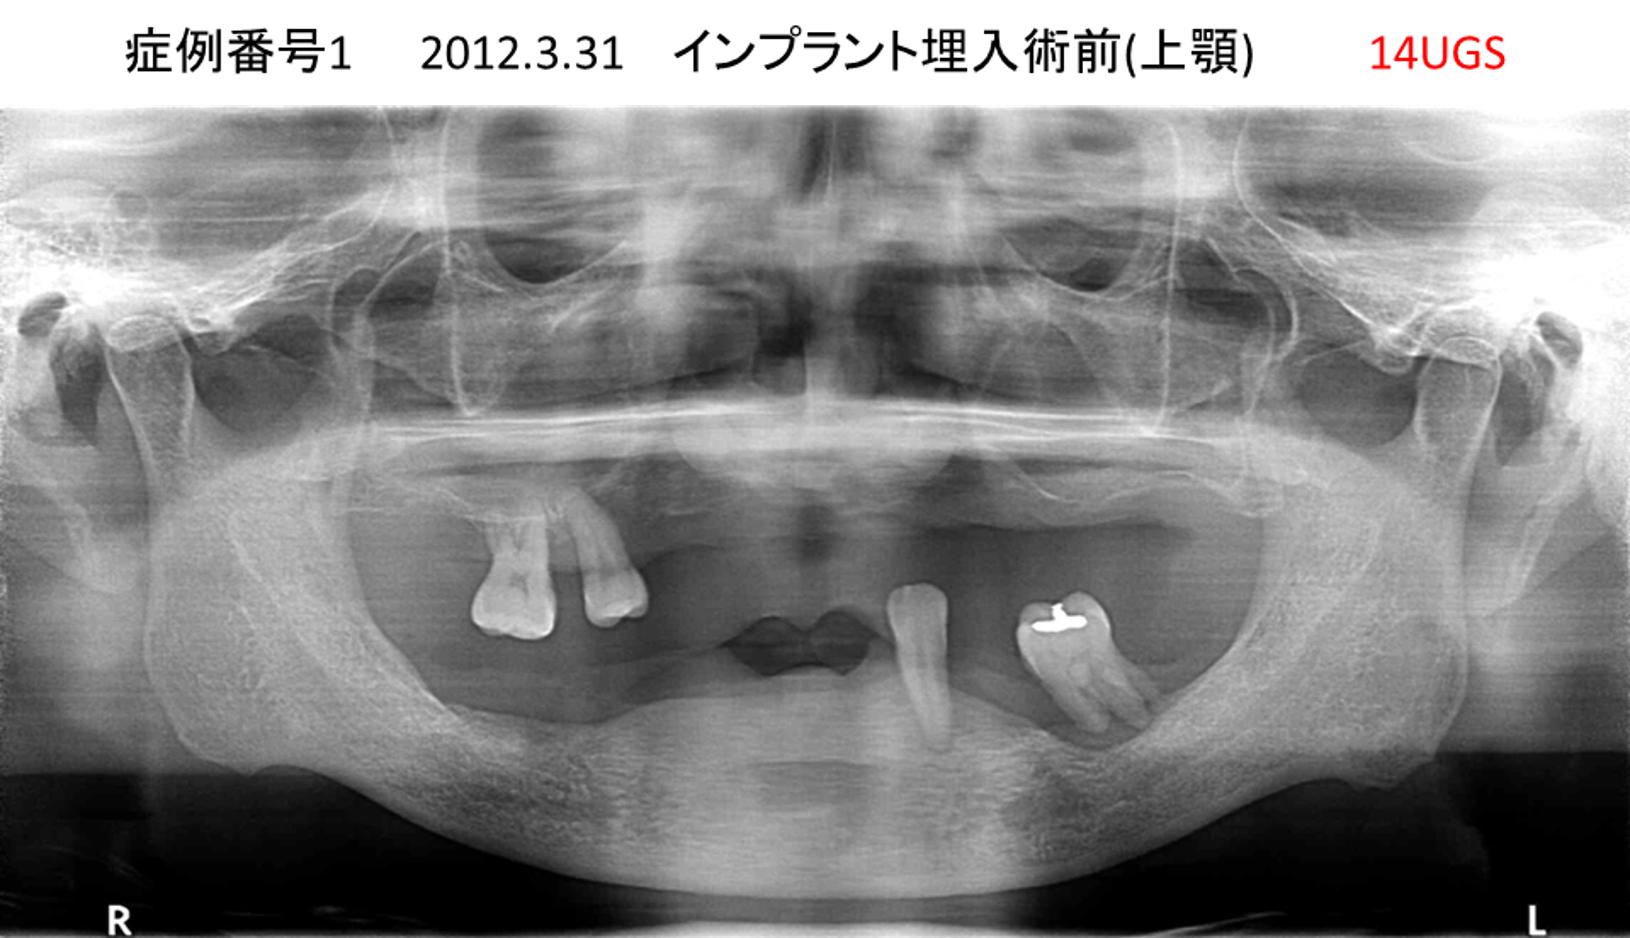

全く噛めない患者様のインプラント症例

| 治療名称 |

インプラントAGC |

| 治療費用 |

860万円+税 |

| 治療期間 |

12か月 |

| 患者さんの症状(主訴) |

全く噛めない、ごはんが後もに食べられるようになりたい、人前で口元を隠したくない |

| 治療内容 |

サイナスリフト、GBR、インプラント、AGC |

| 治療結果 |

しっかり噛めて踏ん張ることができる。食べ物をを選ばなくて済む、何でも食べられる、体重が増えた。見栄えがきれいすぎて自分じゃないみたい |

| 治療の注意点(リスク/副作用) |

インプラントが壊れたら再治療が必要 |